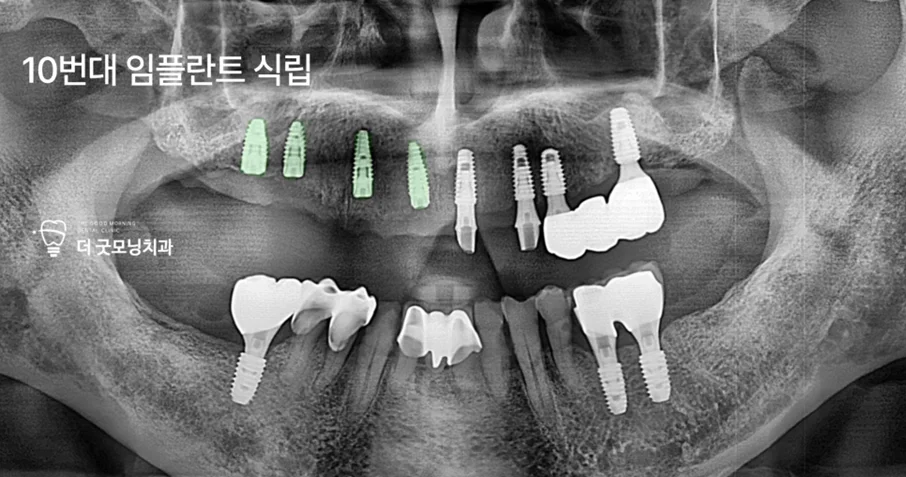

Step 6. 추가 임플란트 식립 — 보험 적용 기간 분리 전략

1년이 경과하여 새로운 보험 적용 기간이 시작되었습니다. 좌측 임플란트의 유착을 확인한 후 로딩 작업을 완료하고, 우측에 4개의 임플란트를 추가 식립했습니다. 이번 수술도 수면마취(의식하 진정) 하에 진행되었습니다.